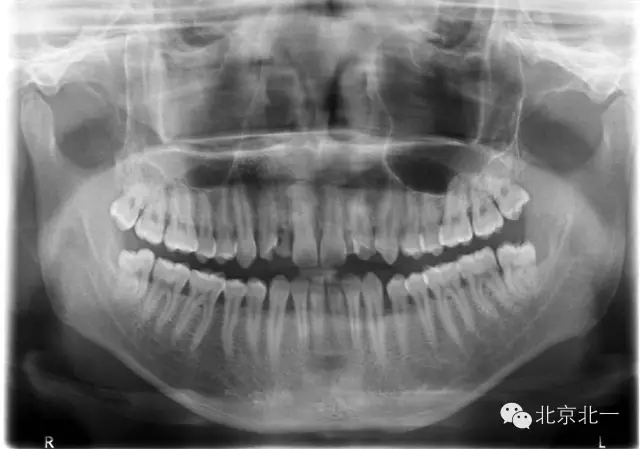

手術(shù)前拍CBCT及全景片、右上中切牙根尖高密度印象。

手術(shù)后拍全景片,順便把滯留乳牙拔除了。